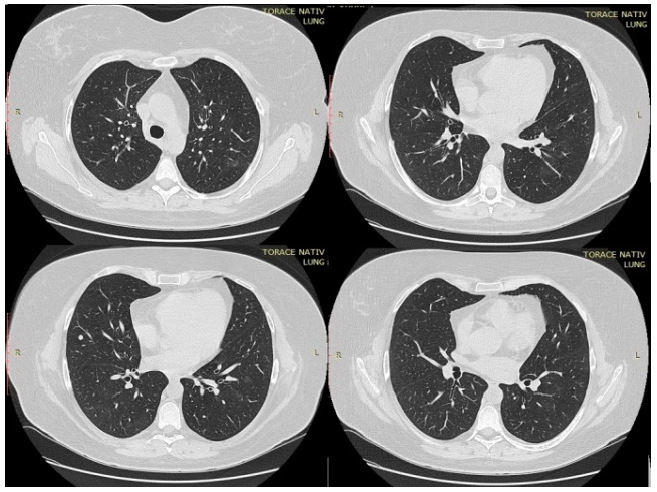

In the first day of hospitalization in our clinic, a native chest CT was performed and both lung fields presented trabecular peribronchovascular condensations (in the anterior upper right lobe segment and in basal segments in lower lobes) (Figure 1). A ground-glass component was associated with central peribronchovascular distribution, which accompanied the trabecular areas described above, with an extension <20%. On the 14th day of treatment, the CT scan was repeated. There was a significant improvement compared to the first scan. Bilateral lung lesions could no longer be observed, with the exception of a 6-mm node in the right middle lobe, probably of fibrous nature (Figure 2).

Four evolutionary stages in CT are described: the incipient/initial stage (0–4 days), the progressive stage (5–8 days), the peak stage (9–13 days) and the resorption stage (>14 days). The evolution of radiological images detected by repeated scans shows that, in about 90% of cases, there is an improvement in lung damage, while 9–10% of cases have a stable condition or imaging damage [17,18]. The imaging behavior of the analyzed patient places them in the 90% group, with quasi-total regression. In various studies, a higher sensitivity of CT was observed of approximately 97% compared to RT-PCR testing, whose sensitivity varies between 45–60%.

Figure 1.

Thoracic CT performed in the first day of hospitalization.